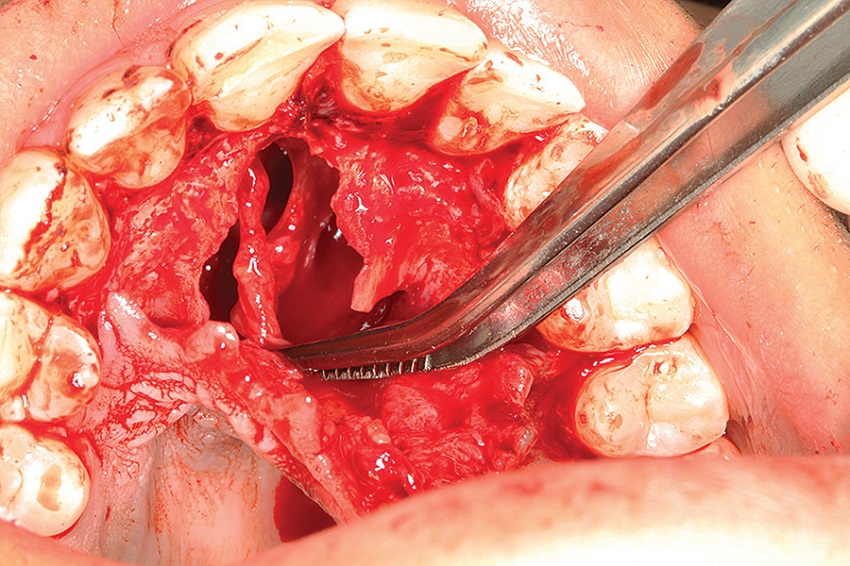

A 25-year-old male patient attended the Stomatology Clinic of the Department of Dentistry of the PUC Minas complaining of a painful swelling in the central region of the hard palate, with three weeks of evolution time. The patient did not present noteworthy systemic alterations. The extraoral examination showed no alterations. In the intraoral examination, we observed the presence of a nodule in the central region of the hard palate, with a soft texture, covered by preserved mucosa and normal coloring (Figure 10). The maxillary occlusal radiograph showed a unilocular radiolucent well-defined lesion, in the anterior region of the maxilla, measuring about 3 cm (Figure 11). Tests of pulp vitality of the teeth close to the lesion were performed to rule out the possibility of inflammatory lesions of endodontic origin. The results were positive, and the diagnostic hypothesis was nasopalatine duct cyst. Under local anesthesia, aspiration of the lesion fluid (positive for translucent fluid) and excisional biopsy were performed, following a surgical protocol similar to the previously reported case (Figures 12 and 13). The material was sent for anatomopathological examination (Figure 14). The histological sections, stained with HE, showed cystic cavity covered by non-keratinized stratified squamous epithelia and fibrous connective tissue capsule with neurovascular bundles, confirming the diagnosis of NPDC.